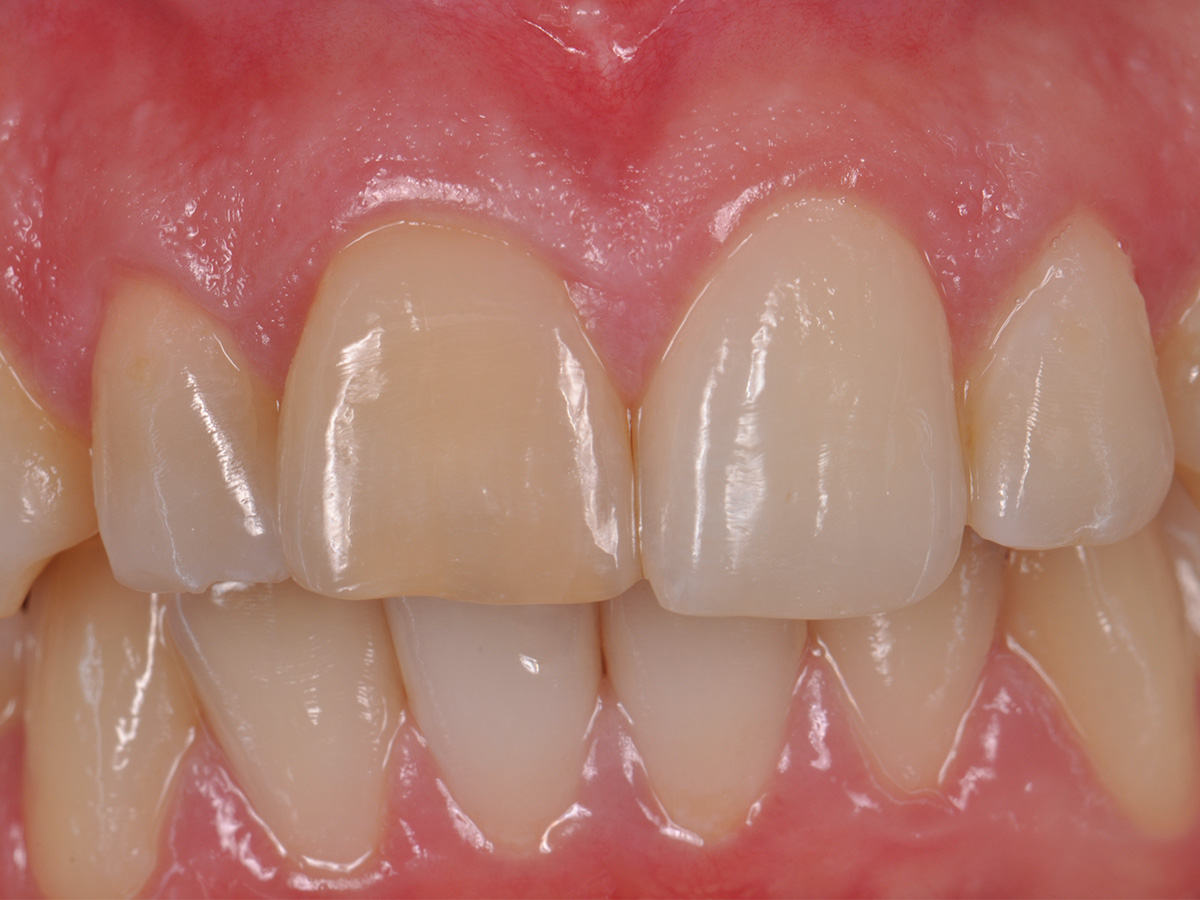

Abbildung 2

Prä-OP: Front nah en face.

Nach einem Zahntrauma im Jugendalter mit anschließender endodontischer Versorgung stellte sich unsere 24-jährige Patientin mit seit einigen Monaten bestehendem, rezidivierendem Druckgefühl und leichten Schmerzen in regio 11 und 12 vor (Abb. 1, 2, 3). Die klinische Untersuchung ergab an Zahn 11 und 12 Lockerungsgrad 1 und, wie zu erwarten, eine negative Sensitivität. Es lag ein leichter Perkussionsschmerz vertikal wie horizontal vor. Die Krone auf Position 11 zeigte eine leichte Verfärbung im Vergleich zu den Nachbarzähnen. Ein OPG ergab eine – in ihrer Ausdehnung nicht sicher zu beurteilende – Aufhellung im Knochenbereich regio 11 und 12 (Abb. 4). Als Nebenbefund waren teilretinierte Zähne 38 und 48 sowie ein vollständig retinierter Zahn 28 als Mikroform nachzuweisen. Ein zusätzlich durchgeführtes DVT zeigte eine große zystische Formation unter Einschluss der Wurzeln 11 und 12, die vom Canalis nasopalatinus bis mesial 13 mit einer kleineren Perforation zum Nasenboden und größeren Perforationen nach vestibulär und palatinal reichte (Abb. 5, 6, 7).

Der postoperative Heilungsverlauf zeigte sich unauffällig. Die Nähte wurden am fünften postoperativen Tag bei reizlosen Wundverhältnissen entfernt. Die pathologische Zystenbalgbeurteilung bestätigte den klinischen Verdacht einer radikulären Zyste. Der Befund wurde nach drei, sechs und zwölf Monaten kontrolliert. Nach drei Monaten konnte keine Lockerung der Frontzähne mehr festgestellt werden. Die Narben zeigten sich blande, ästhetisch unauffällig und trotz der hohen Lachlinie gut unter der Oberlippe verborgen (Abb. 16). Die ossäre Durchbauung des gesamten Zystenbereichs erschien bei der radiologischen Verlaufskontrolle nach einem Jahr vollständig und solide (Abb. 17). Ein Zystenrezidiv konnte bislang klinisch und radiologisch ausgeschlossen werden. Sollten im weiteren Verlauf Zahn 11 und/oder Zahn 12 dennoch erneut Probleme entwickeln und entfernt werden müssen, besteht aufgrund er optimalen ossären Rekonstruktion die Möglichkeit, wiederum ohne die Weichgewebearchitektur zu stören, ein Sofortimplantat mit Sofortbelastung zu setzen und damit die soziale Ausfallzeit für die Patientin auf ein Minimum zu reduzieren. Bei stabilen Verhältnissen nach Operation wurde im Verlauf auf Wunsch der Patientin durch den weiter betreuenden Zahnarzt eine Veneer-Versorgung der Oberkieferfront zur vollständigen Wiederherstellung der ursprünglichen Zahnästhetik geplant.